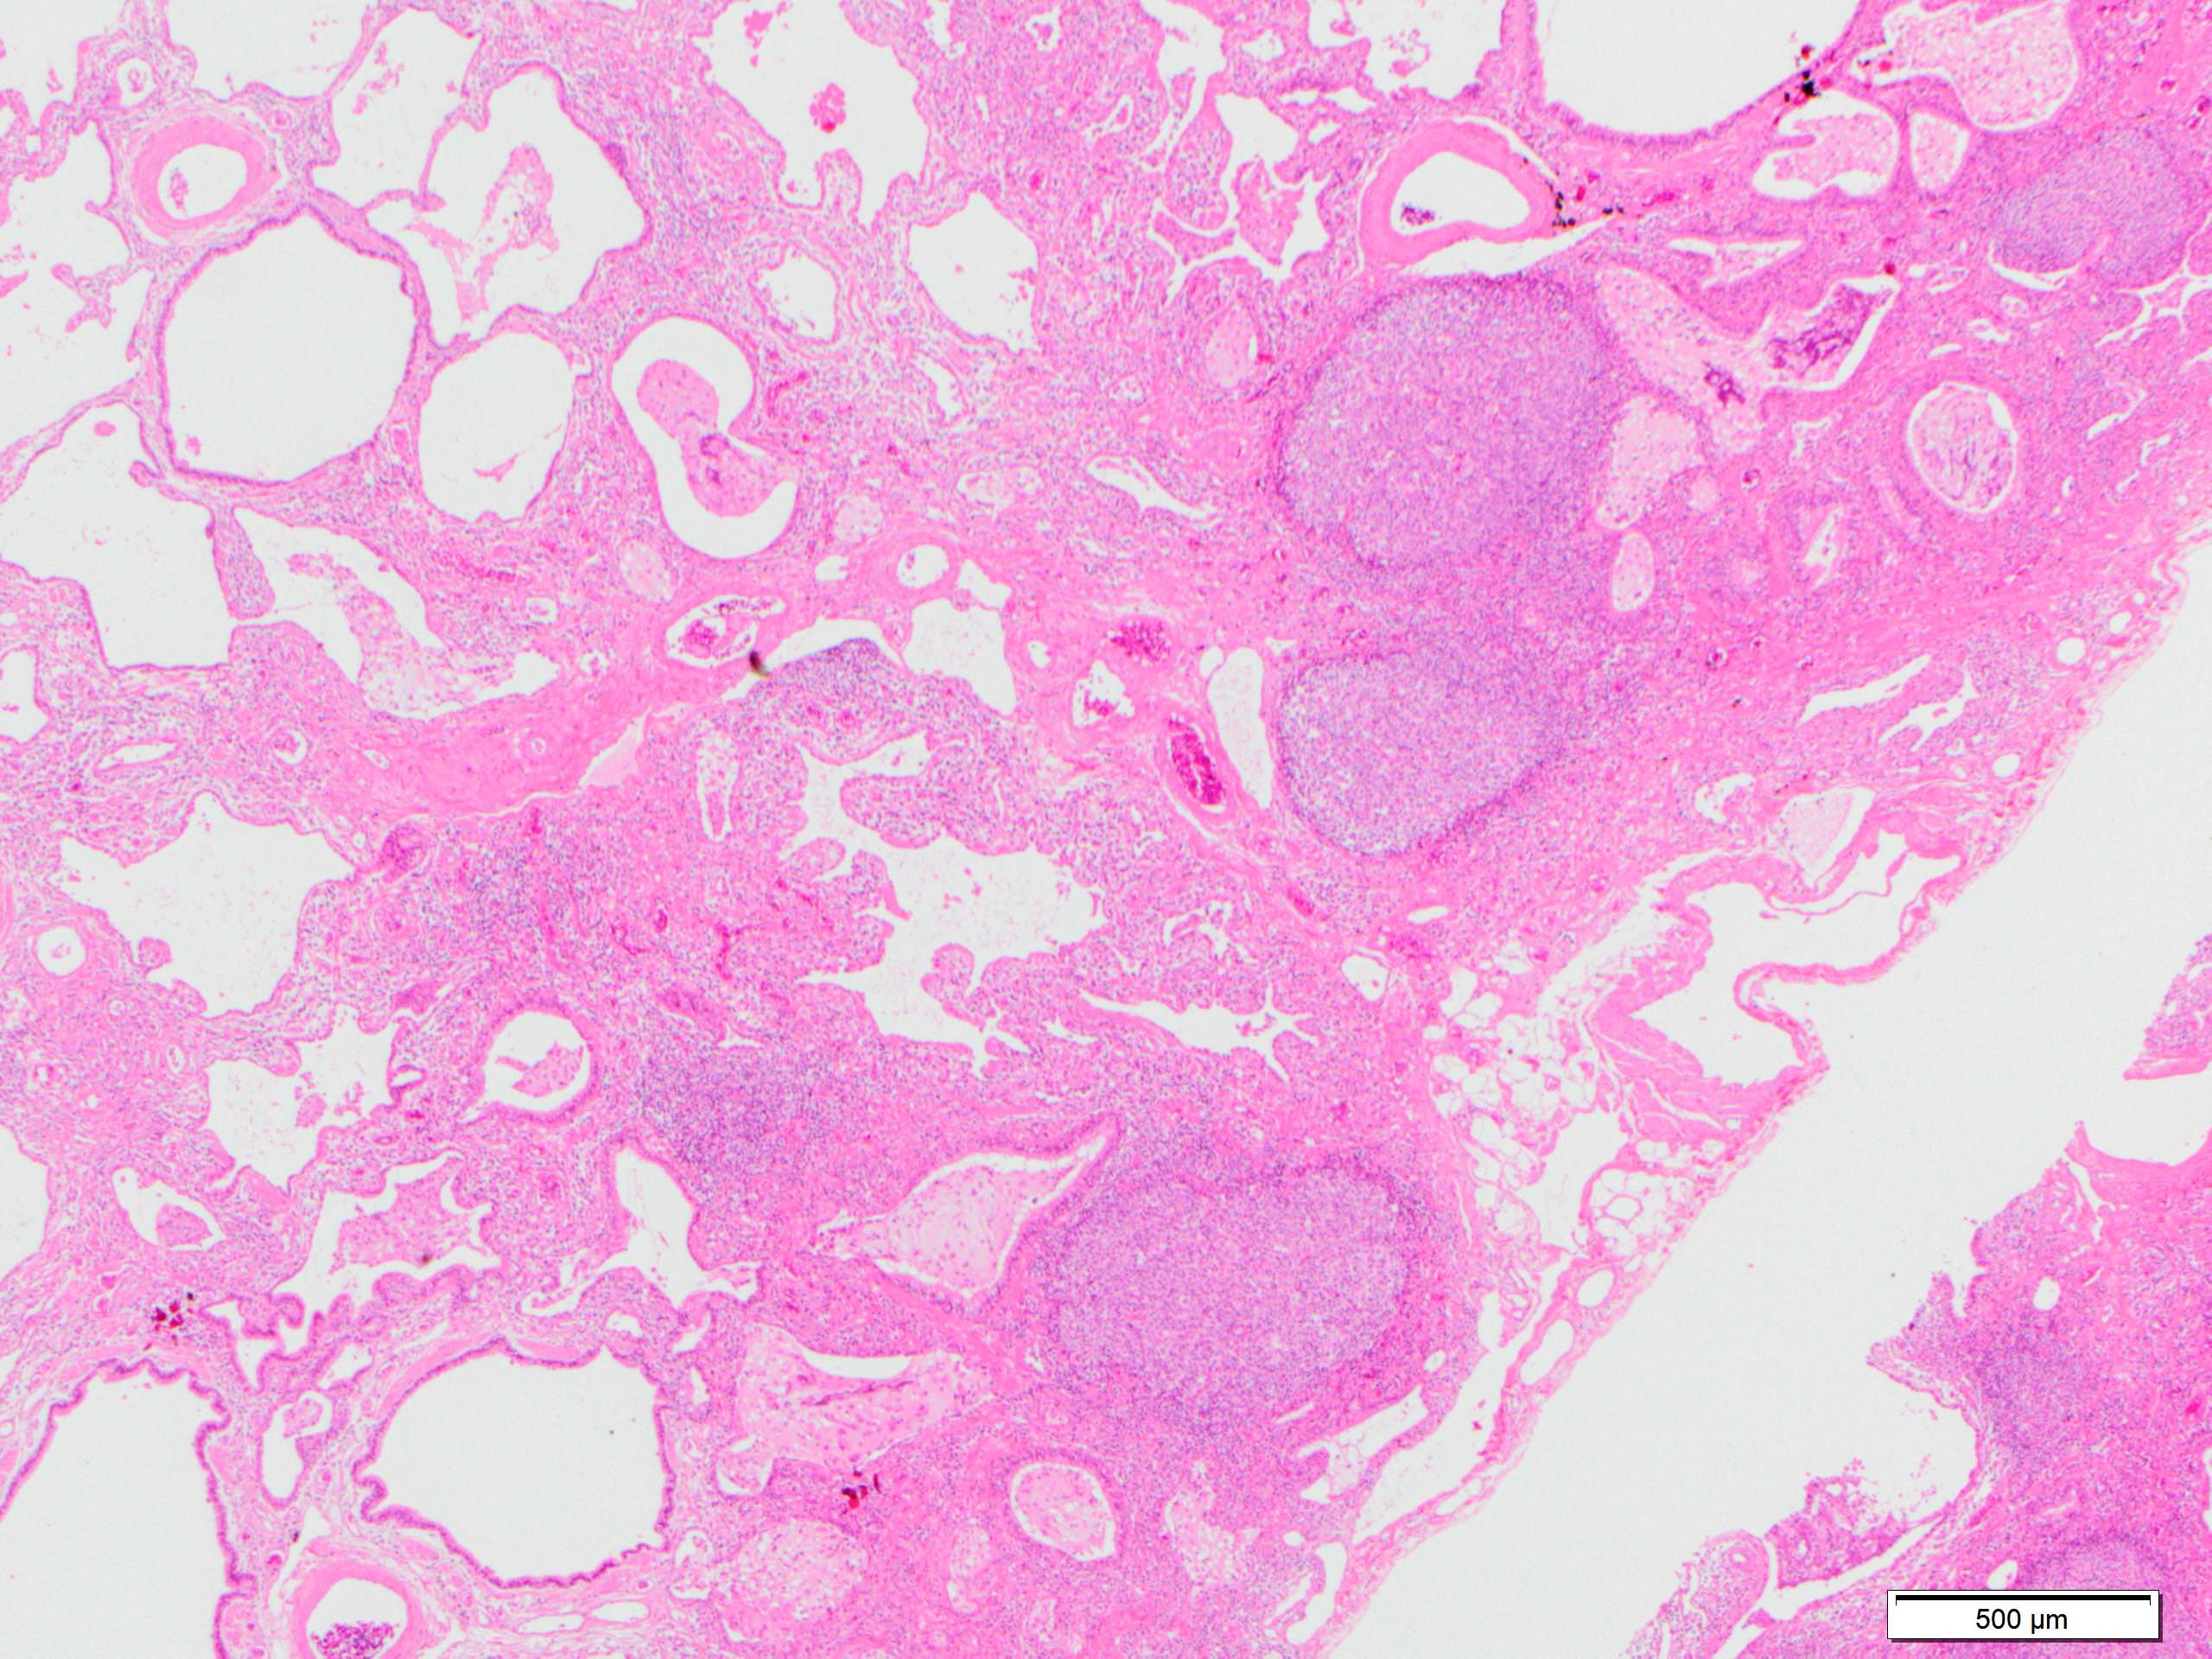

Microscopic (histologic) description

- Since there are few specific findings for NSIP pattern, it is essential to exclude other lung diseases on histology (Am J Respir Crit Care Med 2008;177:1338)

- Characteristic findings of NSIP pattern

- Diffuse and uniform inflammation ("temporal homogeneity") on low power of alveolar wall, bronchovascular bundles and pleura

- There are usually no normal alveolar walls in the affected lobules

- Cellular or fibrotic change

- Lymphocytic or plasmacytic infiltration

- Loose fibrosis

- Lung architecture is frequently preserved

- "Cellular NSIP" or "fibrotic NSIP" can be stated specifically in pathologist report

- Diffuse and uniform inflammation ("temporal homogeneity") on low power of alveolar wall, bronchovascular bundles and pleura

- Features of interstitial pneumonia with autoimmune features (IPAF) (Chest 2010;138:251):

- Lymphoid aggregates with germinal center

- Extensive pleuritis

- Prominent plasmacytic infiltration

- Dense perivascular collagen

- It is quite rare to see pure NSIP on histology - typically there are focal findings of other interstitial lung disease (Histopathology 2014;65:549)

Microscopic (histologic) images

Scroll to see all images.

Contributed by Akira Yoshikawa, M.D.